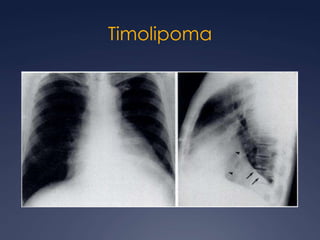

TimolipomaAdolescentes y adultos jóvenes.55% son sintomáticosCompuesto por tejido adiposo maduro y tejido tímico.Gran tamaño